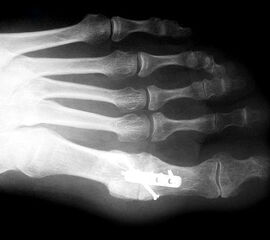

Der Zugang bei der Arthrodese mit den konischen Fräsen erfolgt von dorsal, da das Gelenk dadurch besser exponiert werden kann. Die Streckersehnen werden nach lateral weggehalten. Das Grundglied wird nach der Osteophytenabtragung und der Kapsulolyse scharnierartig nach plantar gekippt. Zentral in die Knochen eingebrachte Führungskirschnerdrähte ermöglichen das Fräsen und Abrunden des Kopfes und das Modellieren der kongruenten Grube an der Zehenbasis. Die Definition der idealen Zehenposition erfolgt wiederum mit einer flachen Unterlage. Diverse Fixationstechniken sind beschrieben 3940. Wir fixieren die Arthrodese mit einer Platte 2,0 (Abb. 9-12) oder 2,7, da mit den kleinen Implantatdimensionen bei Bedarf mehrere unterschiedliche Schraubenpositionen möglich sind.

Die ersten Versuche mit der Prothetik am Großzehengrundgelenk wurden mit metallischen Hemi-Implantaten (Abb. 13, 14) vorgenommen. Eine Studie 47 mit größerem Kollektiv im Langzeitverlauf zeigte befriedigende Resultate, trotzdem hat sich die Technik bis heute nicht wirklich durchgesetzt. Der gleiche Autor verglich die Endoprothese mit der periartikulären Osteotomie und konnte keine wesentlichen Unterschiede feststellen 48. Eine neuere Studie vergleicht die Hemiarthroplastik mit der Arthrodese und der Resektionsarthroplastik und kann keine signifikanten Unterschiede feststellen 49. Metall–Polyäthylen-Paarungen zeigten eine hohe Lockerungsrate der Komponenten, weshalb sich diese Paarung ebenfalls nicht durchsetzte 505152. Am meisten Erfahrung besteht mit der Silikonprothese. Initial als Hemiprothese propagiert 46, wurde wegen mangelhaften Erfolgen 5354 die Totalprothese mit zwei Schäften eingeführt 55. Die Langzeitergebnisse sind widersprüchlich 55565758 so dass wegen der Verunsicherung dieses Model aktuell nicht regelmässig zum Einsatz kommt.